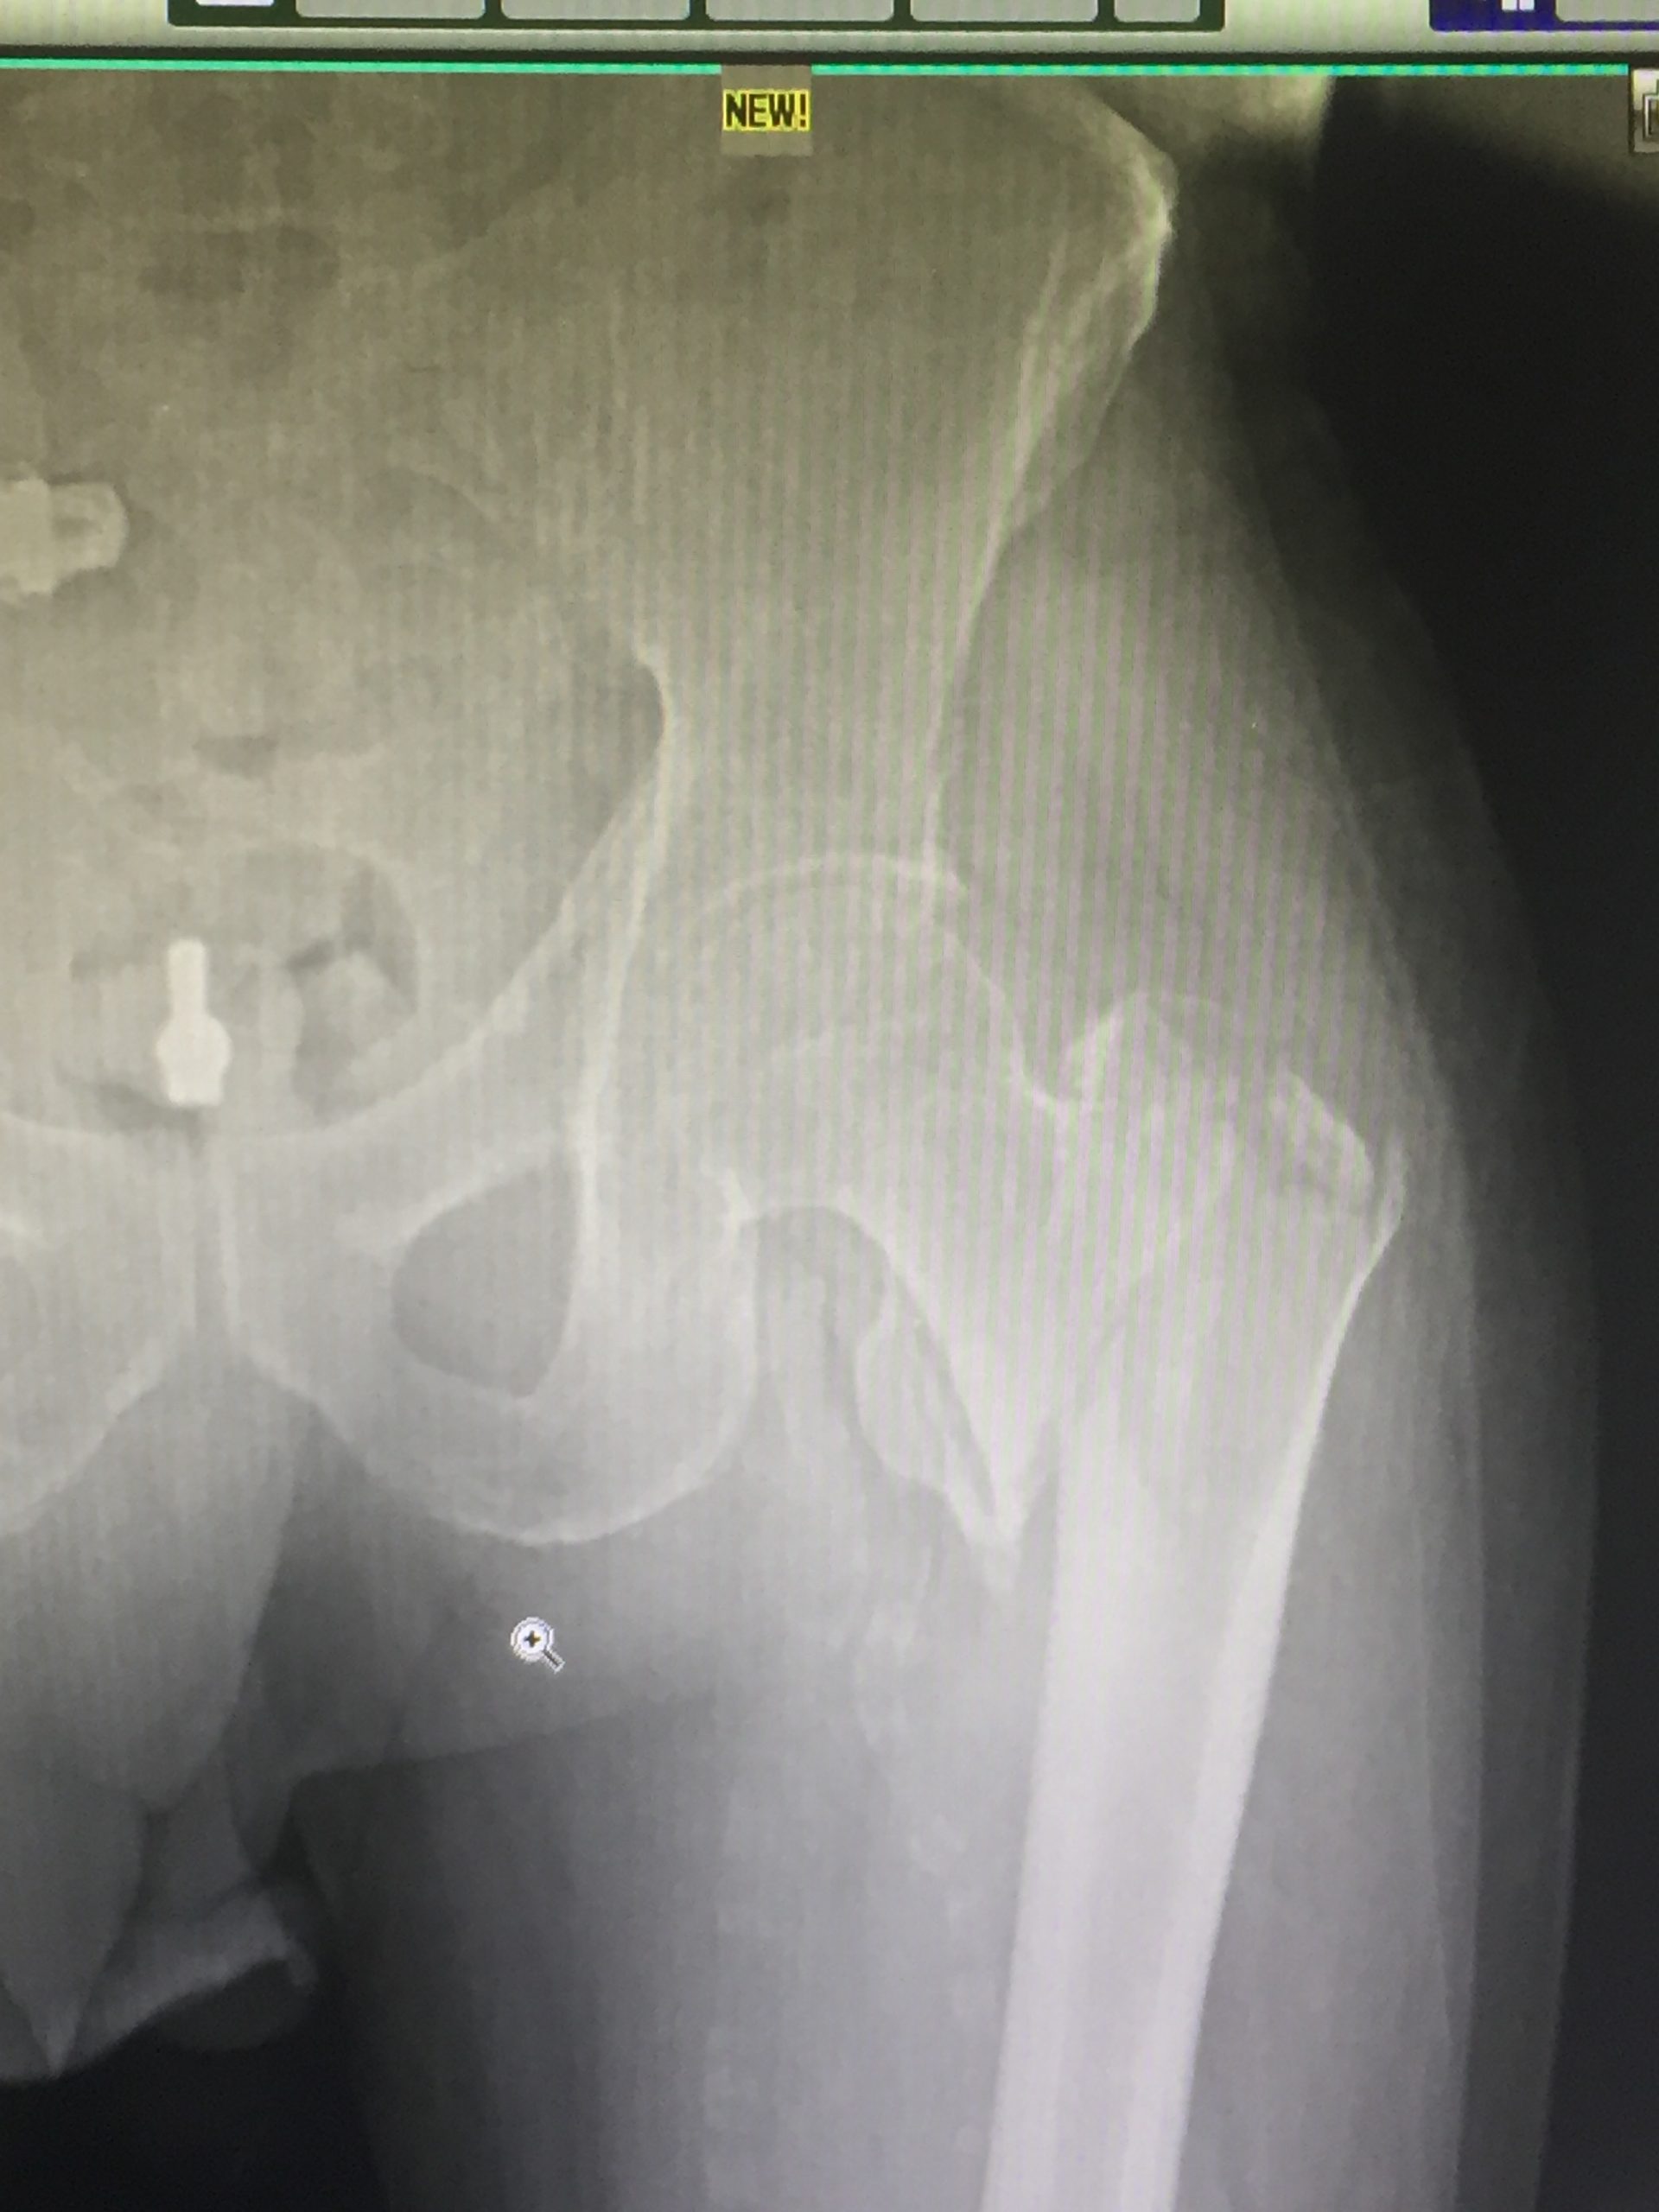

Orthopaedics Home Orthopaedics Orthopedic surgeon studying a x-ray of a broken radius bone in theater after correctional surgery. Man massaging painful wrist on a white background. Pain concept